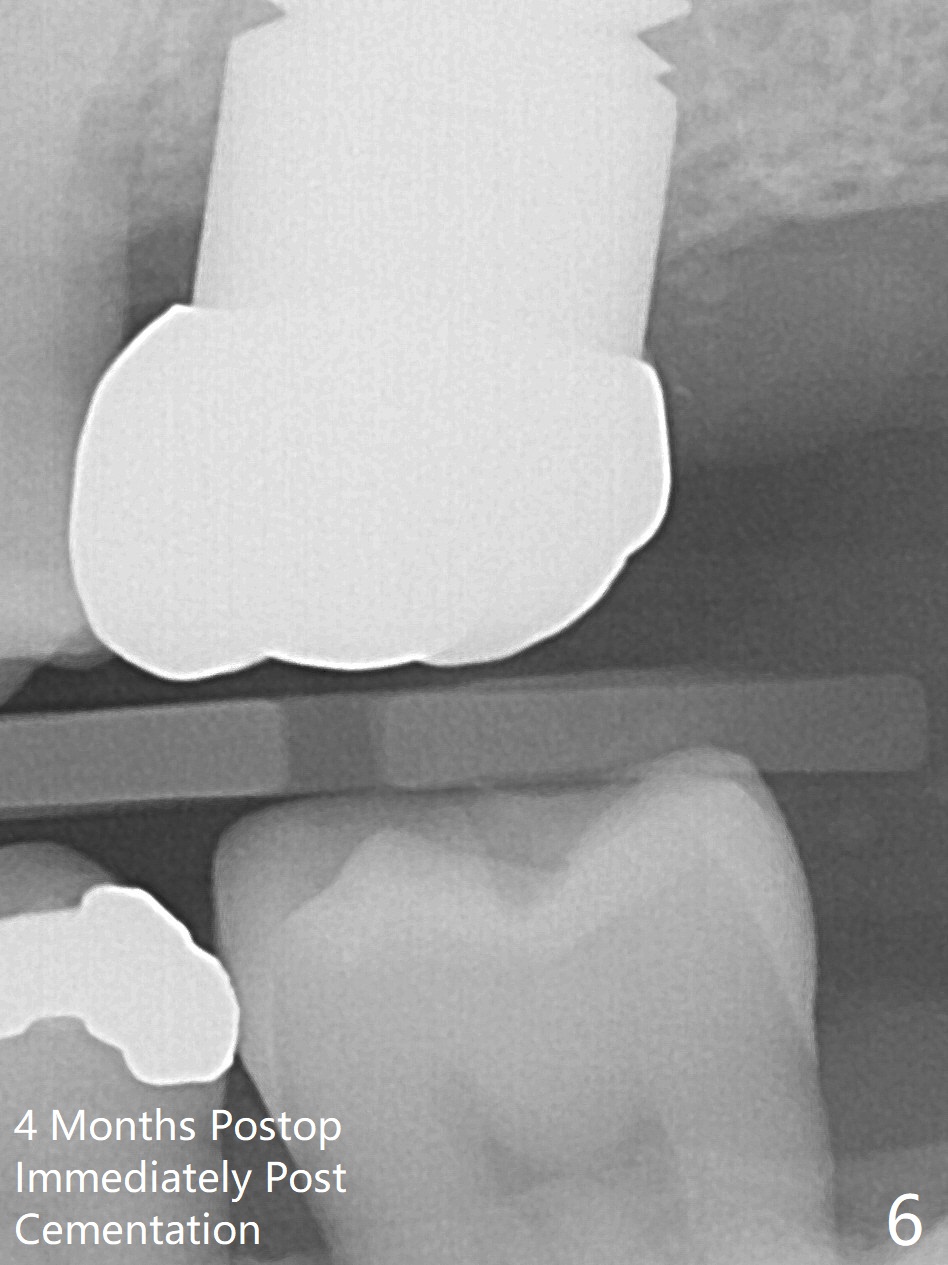

Initially the patient is reluctant to have the crack tooth extracted (Fig.1). Blood drawing for PRF fails. After extraction, the septum is confirmed to be short and thin. The bone density is moderate. When a 3.5 mm drill is being used, the osteotomy perforates into the mesiobuccal socket. A 5x10 mm IS implant achieves minimal stability. As 5.5, 6.0 and 7.0 mm cortical taps are inserted, primary stability is not obtained, as more bone is being removed at the level of the septum. When a 7x17 mm Tatum tapered tap is placed, it looks too small for the socket, as confirmed by measurement of a preop PA (Fig.2). Chronic infection associated with crack syndrome for 2 years may cause bone loss of the socket walls. Since the primary stability of a 8x17 mm tapered tap is not high (Fig.3), a 8x14 mm cylindrical implant is placed (after try in of its dummy one) with > 50 Ncm (Fig.4). The implant engages into the mesial and distal socket walls for stability. A 6x3 mm abutment is placed for an immediate provisional. In spite of difficult manipulation, the sinus membrane remains intact. Vanilla graft is placed for sinus lift and buccal and palatal gaps. Since IS implants are more or less cylindrical and if a 5 mm one does not achieve primary stability, a larger Tatum tapered tap should be tried immediately without using IS cylindrical taps. The patient returns 3 months postop, requesting early restoration before a trip to home country. The provisional has occlusal perforation. Final restoration is cemented nearly 4 months postop (Fig.5,6). The large implant makes the early restoration possible. However there is bleeding on probing palatal 1.5 years post cementation (Fig.7), suggesting palatal thread exposure. Return to Upper Molar Immediate Implant, Prevent Molar Periimplantitis (Protocols, Table), Armaments 6 Xin Wei, DDS, PhD, MS 1st edition 05/07/2018, last revision 05/08/2021